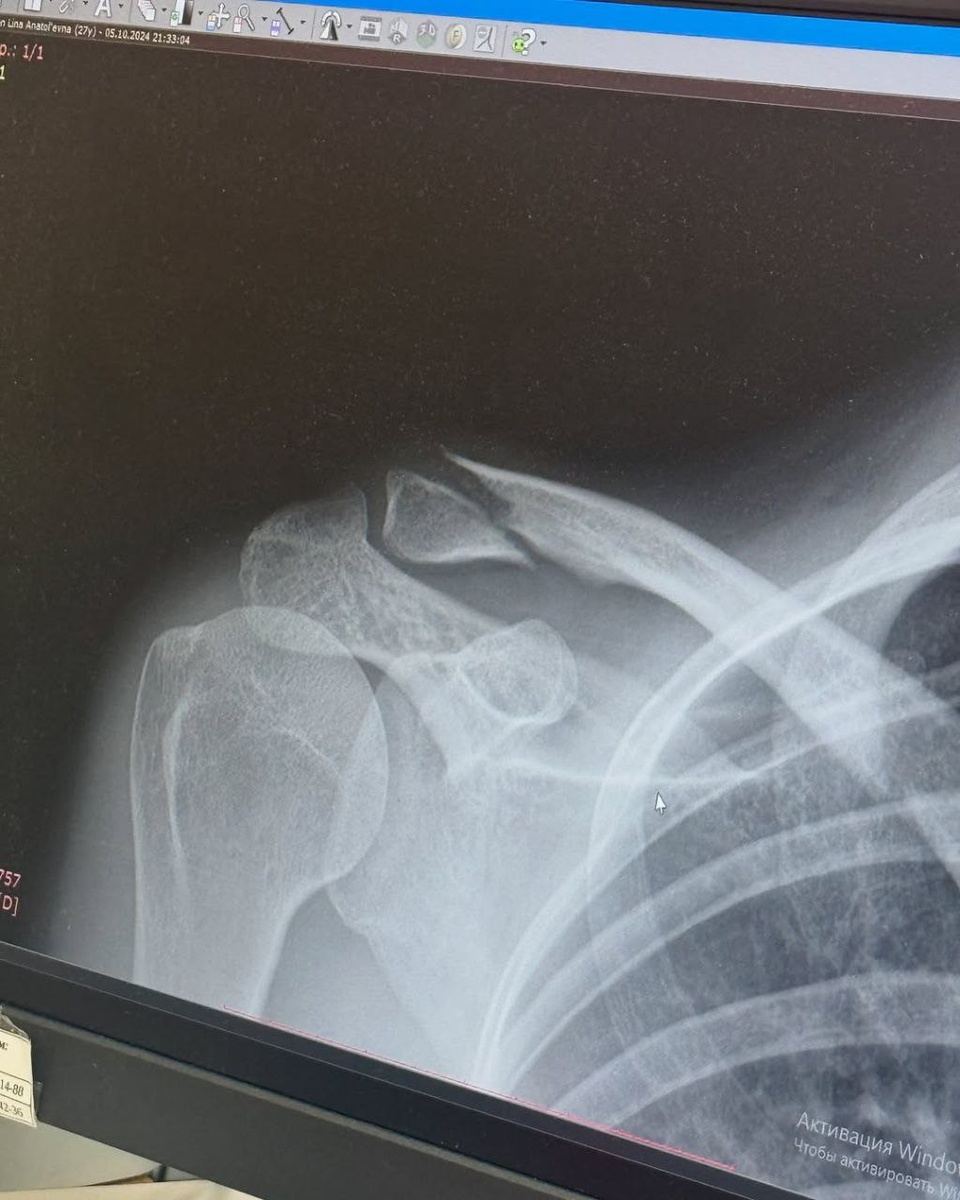

😵‍💫 Муж подвергал домашнему насилию семью, женщина долго молчала и скрывала побои, но теперь боится за свою жизнь и жизнь ребенка. Больше новостей - Темная сторона регионов

😵‍💫 Муж подвергал домашнему насилию семью, женщина долго молчала и скрывала побои, но теперь боится за свою жизнь и жизнь ребенка.